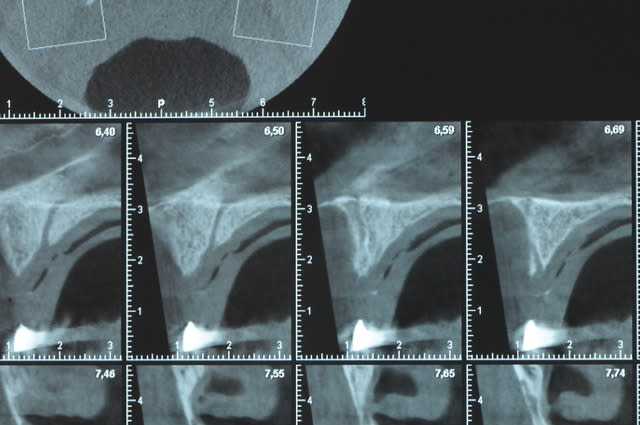

Une petite étude de ton cas D57

Sous réserves bien sur de voir l’animal en vrai

Les zones exploitables radiologiquement parlant:

Coupes implant

2,3 40100

4,96 35130 avec sinus lift mais difficile

5,25 35150

6,02 35130

6,78 35115 après réduction de hauteur de crête

7,26 35115 après réduction de hauteur de crête

8,51 35150

10,43 40115 ou 50115

11,10 40115

Ce qui nous fait 9 implants possible évidement avec un comblement de sinus on augmenterait encore les zones implantable mais ce n’est pas le but recherché, avec 8 (4+4) il doit être possible de faire une belle barre support de complet